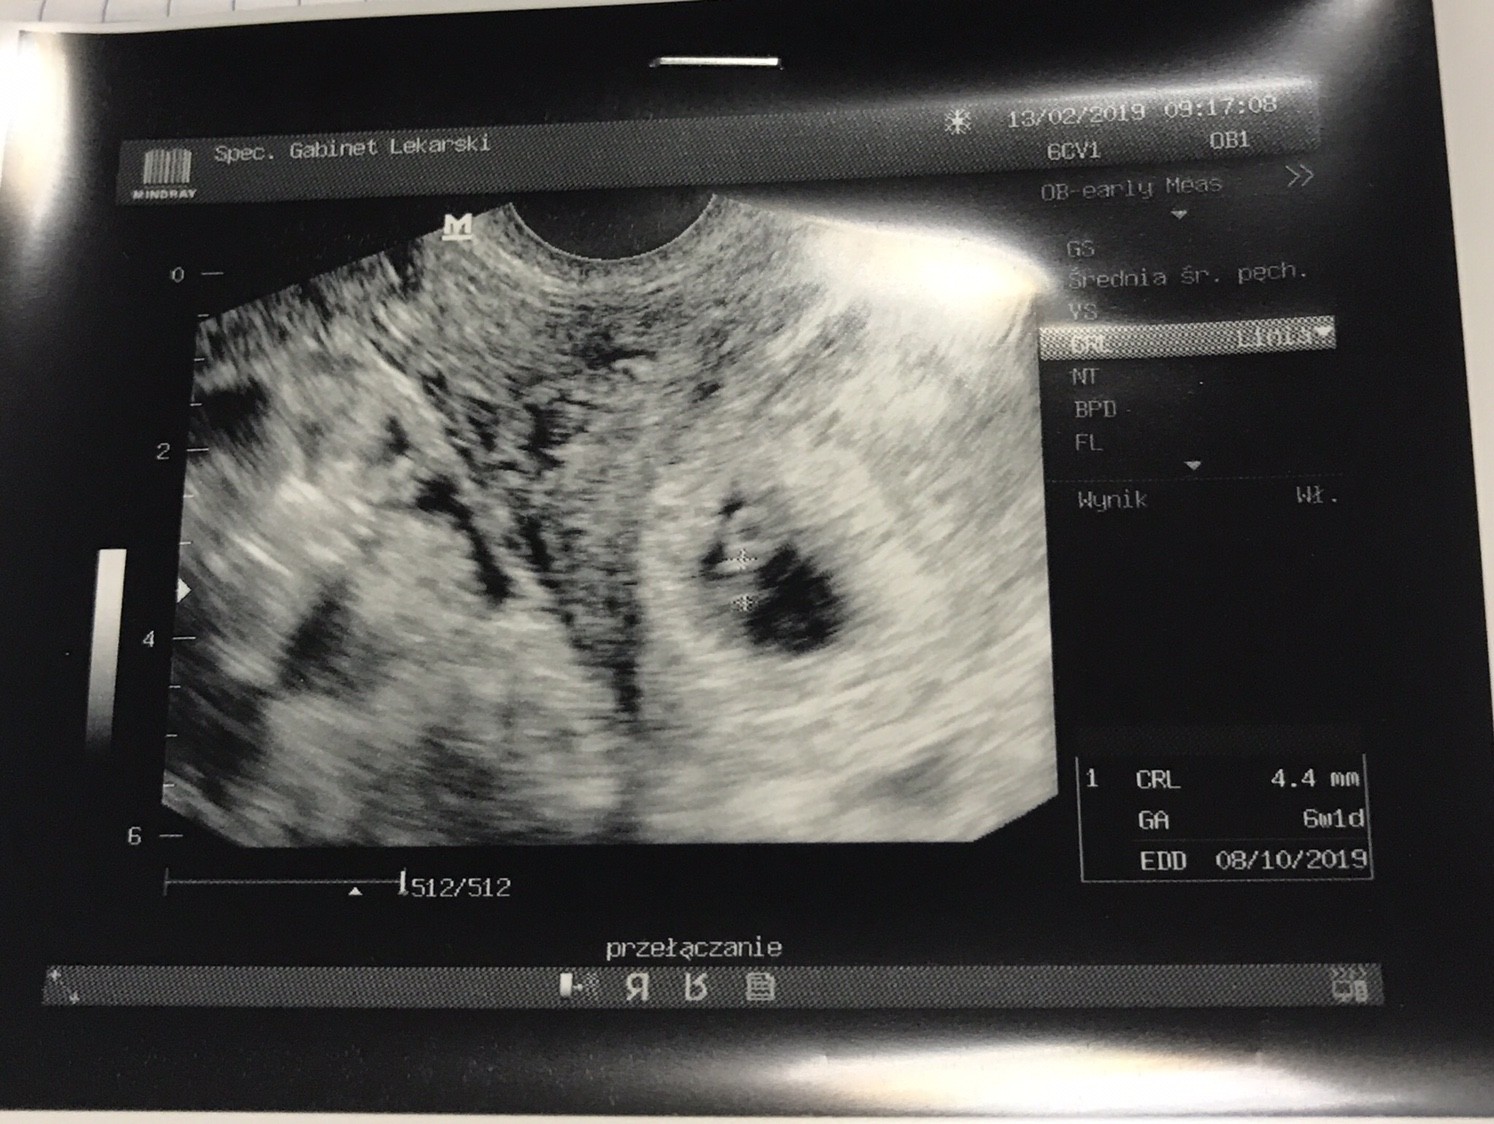

Jest zarodek.

Jest serduszko.

Wedlug usg 6t1d. Termin Wedlug OM 23.09. Wedlug usg na pazdziernik..

Mlode ma 4,4mm

IMG_4981.JPG